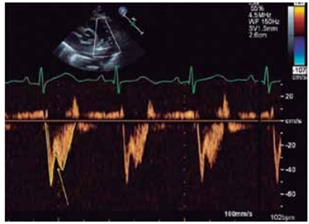

Observe a imagem.

(Arquivo pessoal; imagem utilizada com autorização)

A seta indica: